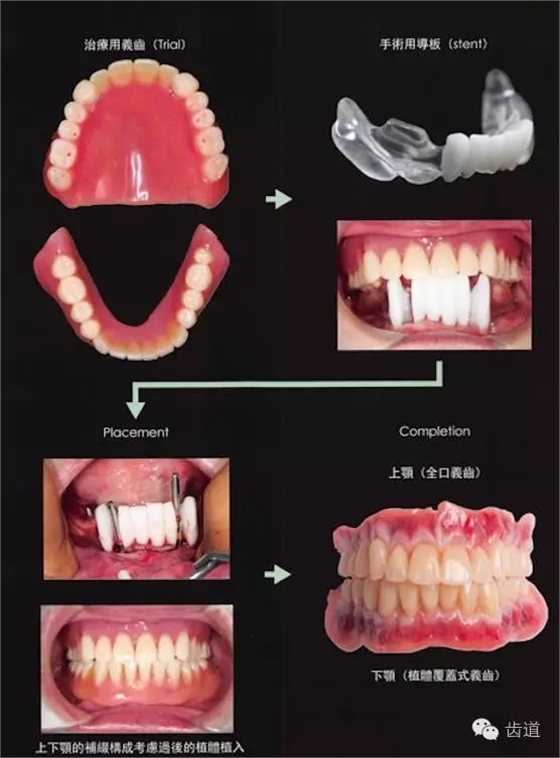

阿部老師告訴我們 為了避免給修復(fù)醫(yī)生制造疑難雜癥,正確的種植修復(fù)步驟是這樣的! 常規(guī)制作上下頜義齒 (天哪!再高大上的種植技術(shù),也解救不了不懂全口義齒的牙醫(yī)) 制作與對頜關(guān)系正常的手術(shù)導(dǎo)板 植入植體 完成最終修復(fù)!